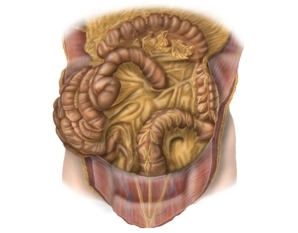

• Anastomoses entre ramos da artéria mesentérica superior e inferior (artéria cólica média e esquerda, respectivamente) perto da flexura esplênica (anastomose de Riolan).

• Hemicólon esquerdo, cólon sigmoide e reto superior supridos pela artéria mesentérica inferior e seus ramos: artéria cólica esquerda, artérias sigmoides com artéria marginal de Drummond, artéria retal superior.